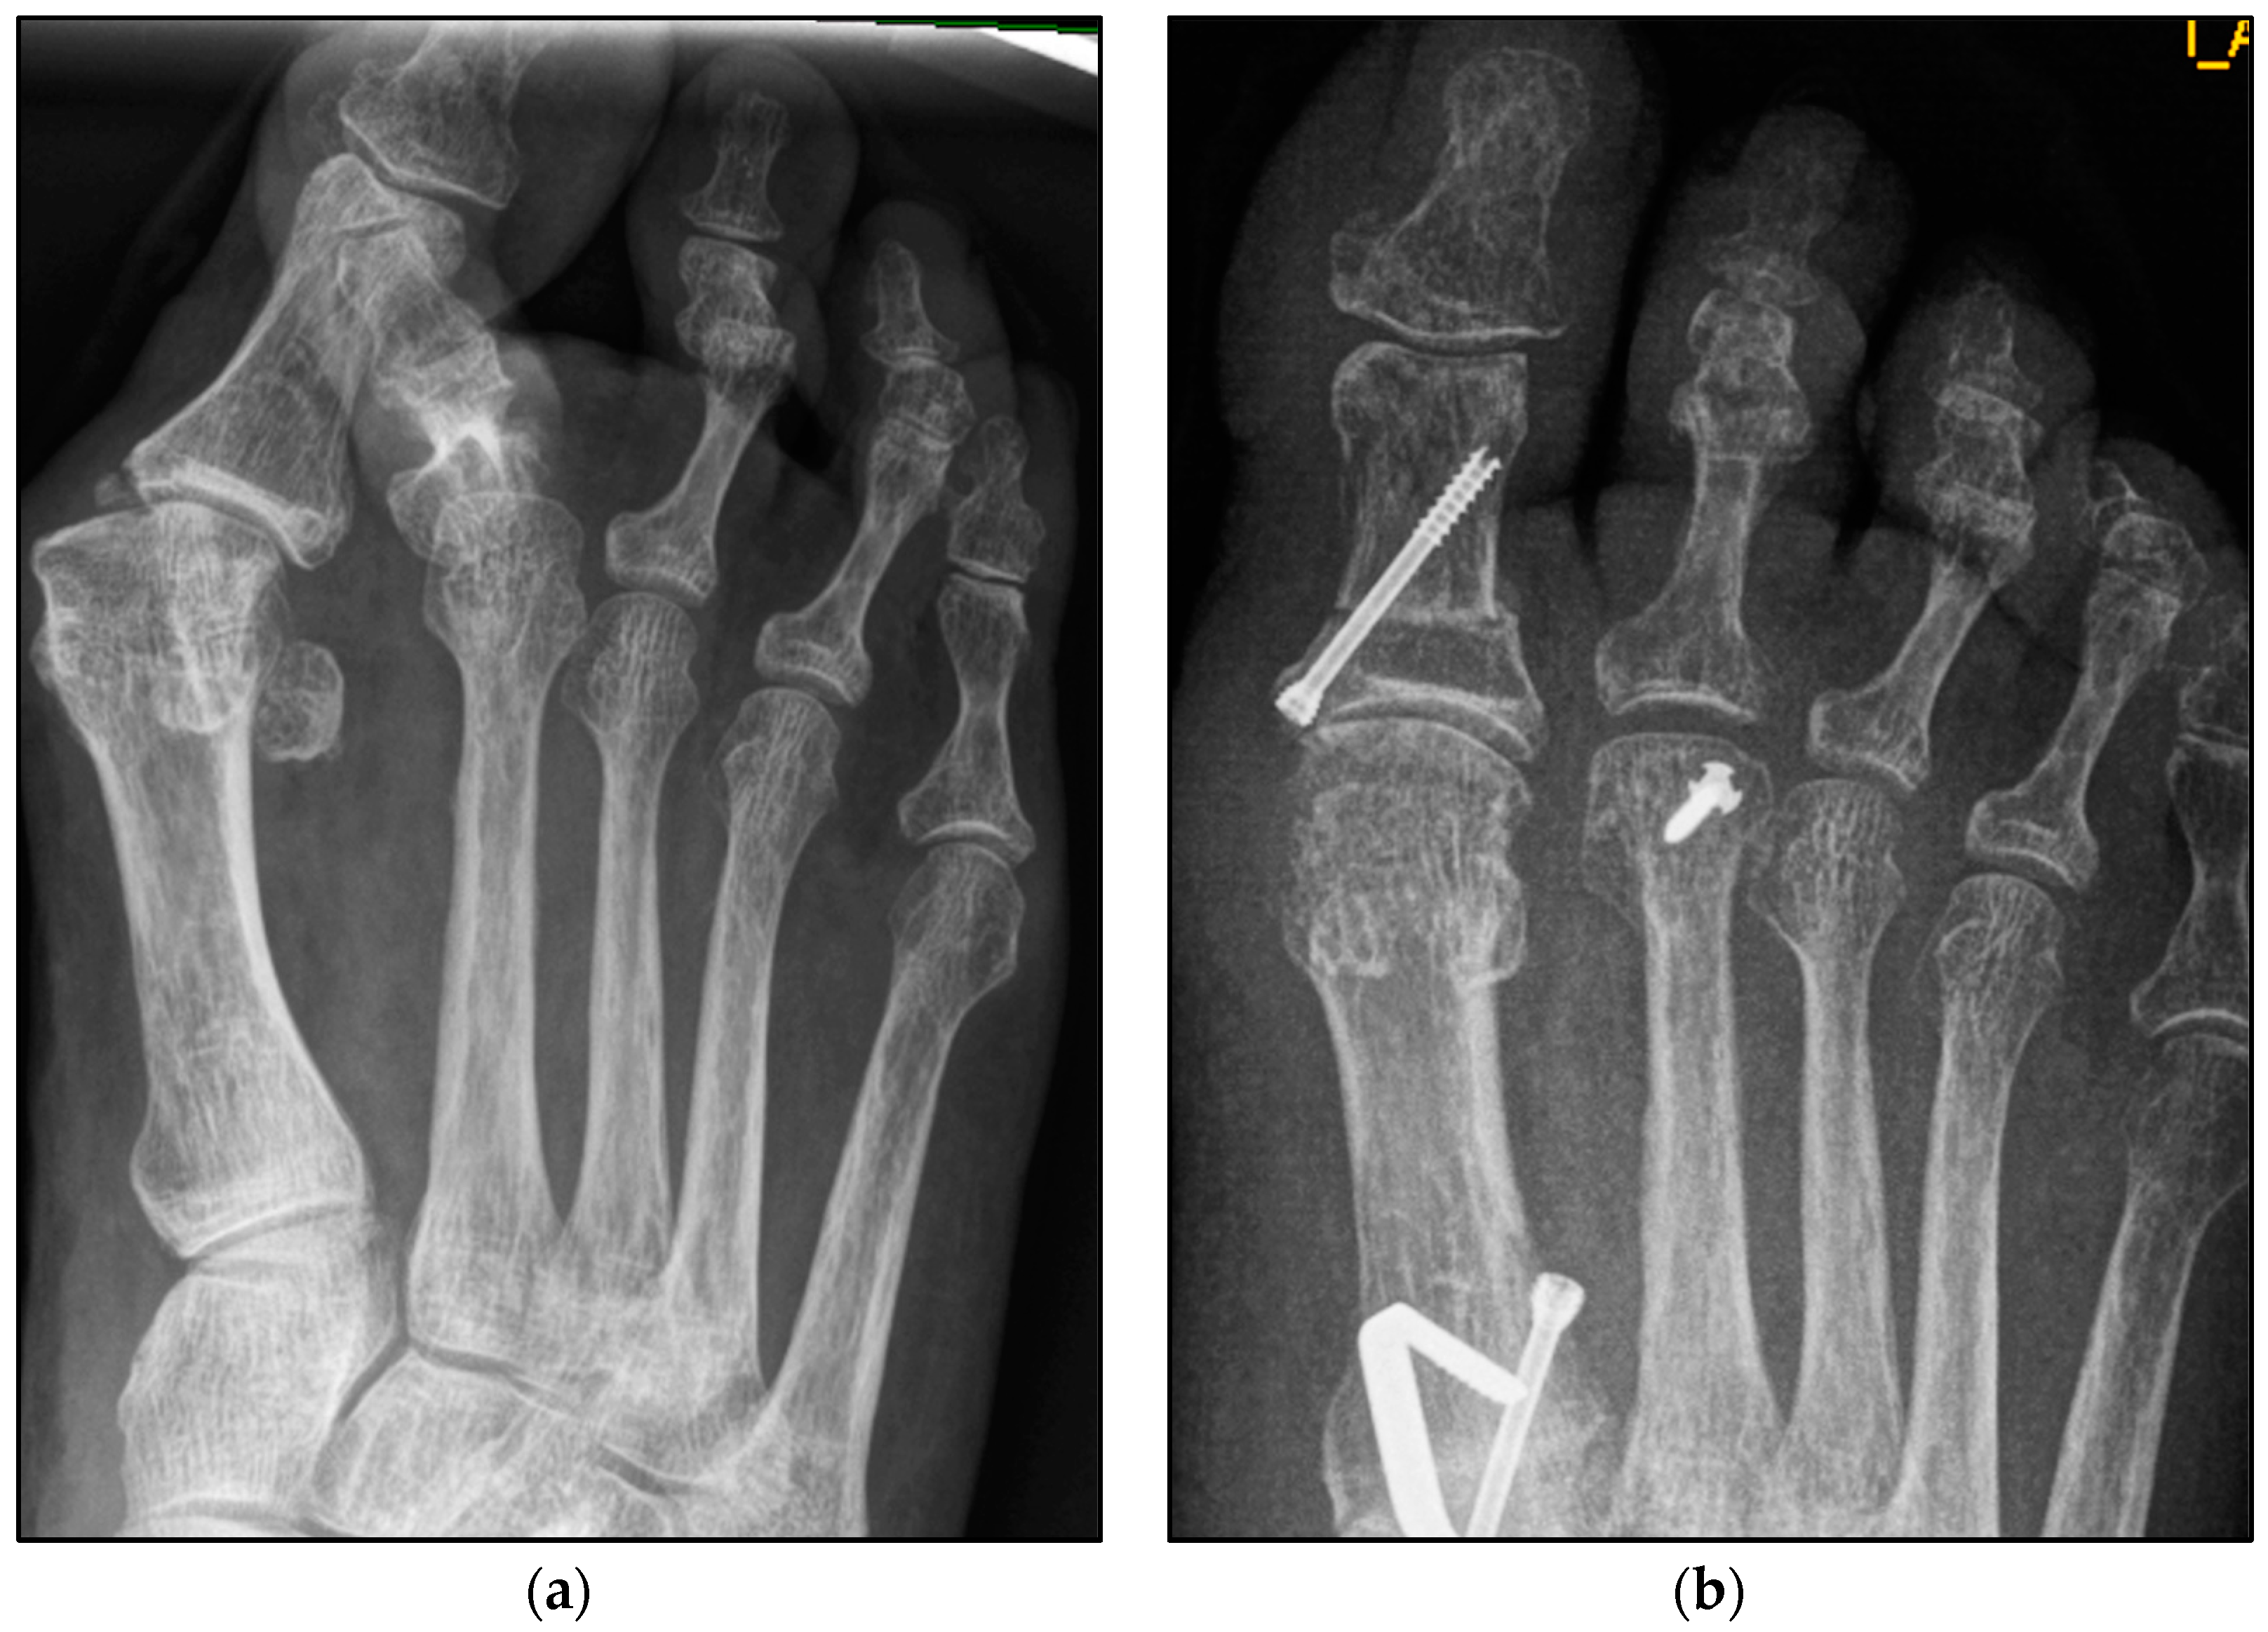

Figure 4.

Pre- and postoperative radiographic results of combined hallux valgus surgery and Weil osteotomy of metatarsal 2 (group A with screw fixation), right foot. (a) Weight-bearing radiograph: anteroposterior view preoperative, (b) weight-bearing radiograph: anteroposterior view, 3 months postoperative.

We collected the following data from the weight-bearing dorsoplantar foot radiographs after a mean follow-up period of 16 weeks (3.6 months). With no significant difference between groups, the mean MTP angle changed from 9.24° to 12.99° preoperative to postoperative (medial deviation: −n, lateral deviation: +n). As can be seen from the mean SEM in Table 2 and Figure 4 and Figure 5, the maximum medial and lateral deviations from pre- to postoperative were significantly different. The mean MTP only changed from 9.3 to 12.9 and was in the range of a mild lateral deviation. This was also observed equally in both groups (p > 0.05). Of note, the postoperative visibility of the joint space was documented significantly more often in the group without screw fixation; this means the space between the subchondral bone of the metatarsal and the toe was seen without overlay (p < 0.05).

The underlying assumption of our study and the knowledge gained from our results can be further elaborated upon. An inharmonious transverse plane alignment can also be corrected with Weil osteotomy and does not require osteosynthetic fixation of the displaced metatarsal head [24]. The results confirm, based on postoperative weight-bearing radiographs, that the surgically induced correction is maintained regardless of screw fixation. An objectifiable criterion was the metatarsophalangeal angle measured pre- and postoperatively using weight-bearing radiographs in the dorsoplantar view (Figure 1 and Figure 2). In both treatment groups, it was possible to bring the maximum axis deviation closer to the mean value; the mean difference between pre- and postoperative metatarsophalangeal angle was only 3.8°. On average, 10.6 degrees were required to achieve the desired surgical result, regardless of screw fixation (Figure 4 and Figure 5). However, the significantly higher possibility of viewing the affected metatarsal joint space postoperatively can also be considered a successful outcome of the restoration without screw fixation. The visibility of the articular surface, in turn, proves the centering of the metatarsal head in the transverse plane as well as a sufficient correction in the sagittal plane (Figure 6 and Figure 7) [25]. Again, the inability to view the joint space indicates that inadequate correction of the claw toe deformity as well as the metatarsal, which was considered “too long”, was performed [1,14,26].